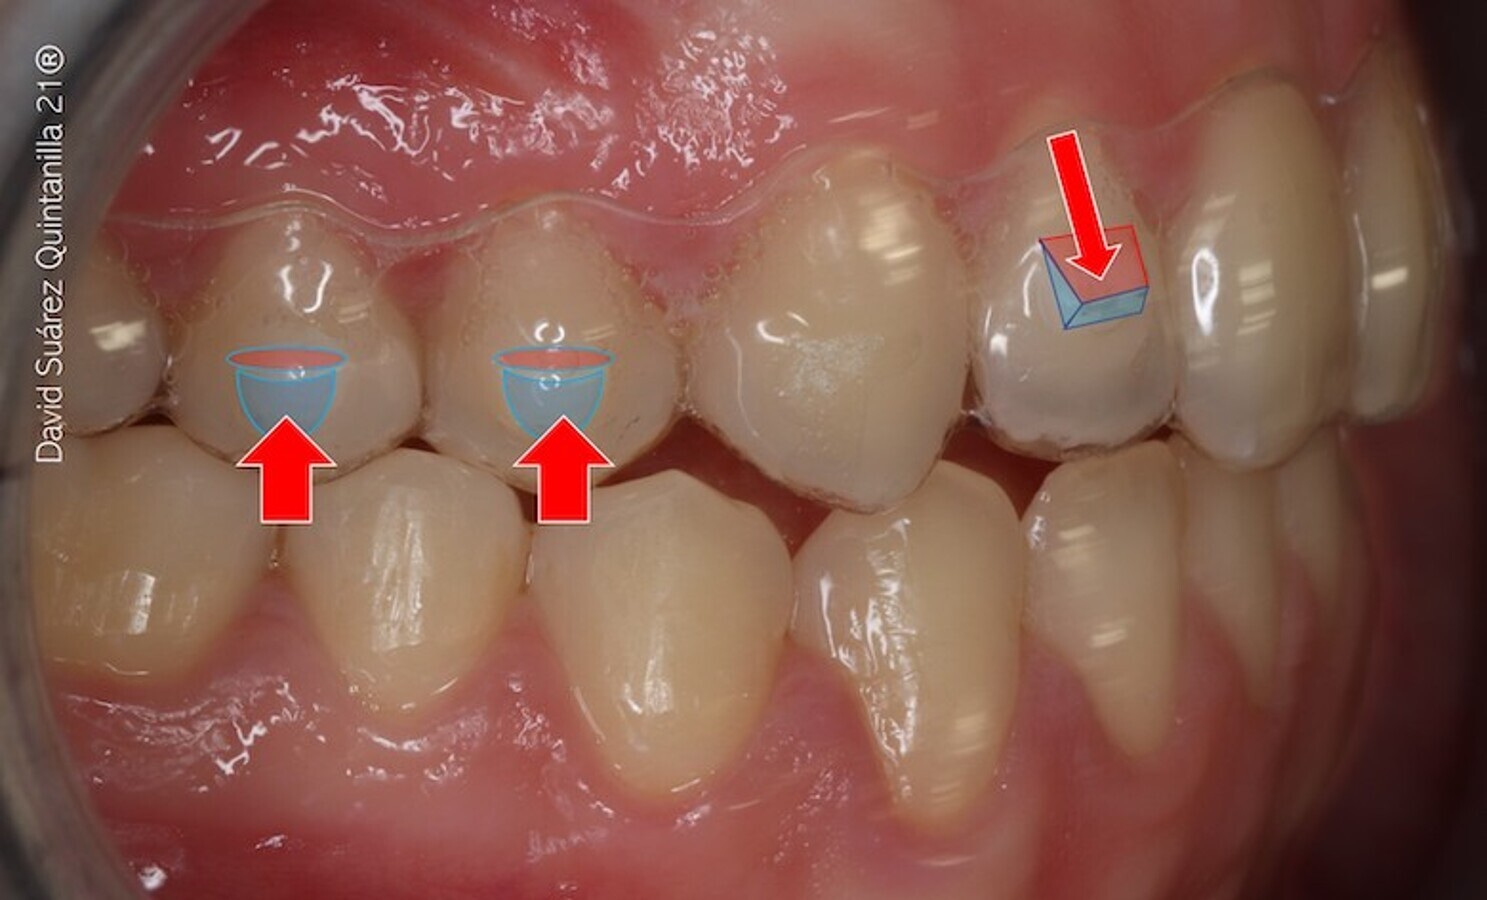

La torsión pura obedece a la relación de momento/fuerza mayor de 1 y se caracteriza porque el centro de masa se desplaza al borde incisal/oclusal y el máximo movimiento dentario se produce en el ápice; si hay movimiento o desplazamiento coronal hacia vestibular (el arco no está cinchado o ligado en distal), el movimiento no es de torsión, sino de inclinación coronal. El mecanismo de torsión en dientes posteriores es similar cuando hablamos de ortodoncia fija o de alineadores (figuras 31 a 33) y se centra, en estos últimos, en la aplicación de un par de fuerzas sobre un prisma rectangular (en la técnica multibrackets se hace con el doblado del alambre alrededor de su eje mayor o incorporando una determinada angulación en el bracket).

Figuras 31-33. El mecanismo de torsión en dientes posteriores es similar cuando hablamos de ortodoncia fija o de alineadores.

El mecanismo de torsión en dientes posteriores es similar cuando hablamos de ortodoncia fija o de alineadores.